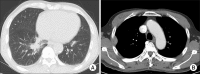

Immunoglobulin G4 (IgG4)-related disease is a newly recognized condition characterized by fibroinflammatory lesions with dense lymphoplasmacytic infiltration, storiform-type fibrosis and obliterative phlebitis. The pathogenesis is not fully understood but multiple immune-mediated mechanisms are believed to contribute. This rare disease can involve various organs and pleural involvement is even rarer. We report a case of IgG4-related disease involving pleura. A 66-year-old man presented with cough and sputum production for a week. Chest radiography revealed consolidation and a pleural mass at right hemithorax. Treatment with antibiotics resolved the consolidation and respiratory symptoms disappeared, but the pleural mass was unchanged. Video-assisted thoracoscopic surgery was performed. Histopathology revealed dense lymphoplasmacytic infiltration and storiform fibrosis with numerous IgG4-bearing plasma cells. The serum IgG4 level was also elevated. Further examination ruled out the involvement of any other organ. The patient was discharged without further treatment and there is no evidence of recurrence to date.